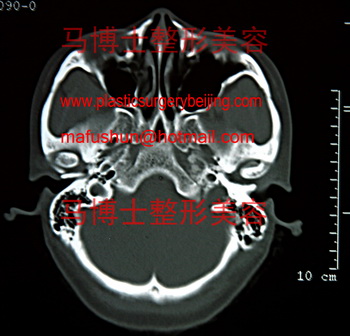

上述实际测量大体从外观上说明了什么情况下可以做颧部缩小术。但是不是面部的比例不匀称是由骨骼的结构比例不协调引起的呢?软组织手术,还是骨骼手术才能改善面形?这需要进行面部的骨骼结构测量。目前最好的方法是进行CT颌面扫描,利用三维重建和断层图像,对面中部骨骼的宽度、颧骨和颧弓的厚度及对称性进行测量,所得结果与同种族、同地区、同性别的参考值进行比较和分析。可以比较精确地计算手术时的截骨量和骨骼移动量。充分的术前设计,确认手术适应证,并确定最佳手术方案,方可保证手术的成功和术后效果满意。

右侧CT显示颧骨颧弓较右侧者宽,颧弓向两侧突出,两颧弓之间的距离大。